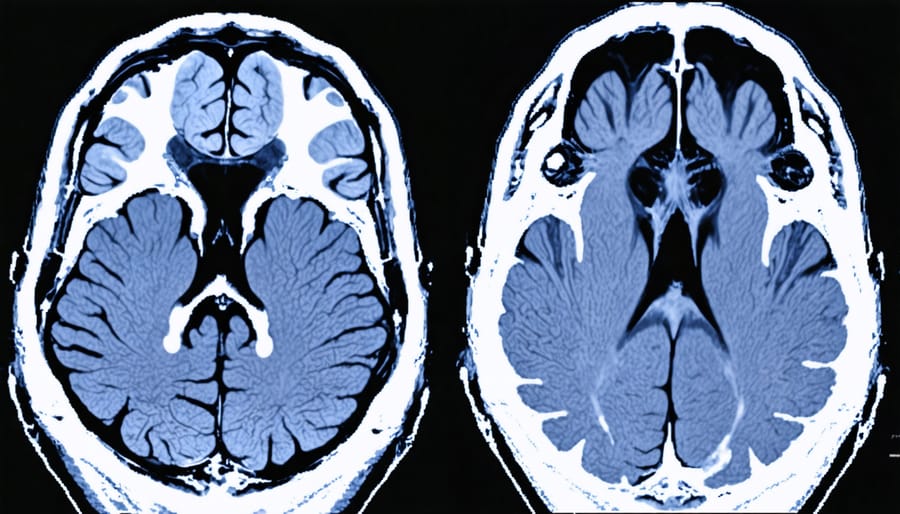

Image recognition technology is particularly powerful in medical diagnosis. It can analyze X-rays, MRIs, and CT scans to detect abnormalities like tumors, fractures, or signs of conditions like pneumonia. This technology acts as a second set of eyes for healthcare providers, helping them make more accurate diagnoses and develop better treatment plans.

AI has revolutionized how healthcare providers analyze medical images, making diagnosis faster and more accurate. When you get an X-ray, MRI, or CT scan in Alberta’s hospitals and clinics, AI technology can help radiologists spot potential health issues that might be difficult to detect with the human eye alone.

These AI systems are trained on millions of medical images, learning to recognize patterns that indicate various conditions. For example, in chest X-rays, AI can help detect early signs of lung cancer, pneumonia, or heart problems. With mammograms, AI assists in identifying potential breast cancer markers that might otherwise be missed.

The technology doesn’t replace healthcare professionals but works alongside them as a powerful tool. Think of it as a second set of highly trained eyes that can process images in seconds, highlighting areas that need closer examination. This helps your healthcare team make more informed decisions about your care while reducing the chance of missed diagnoses.